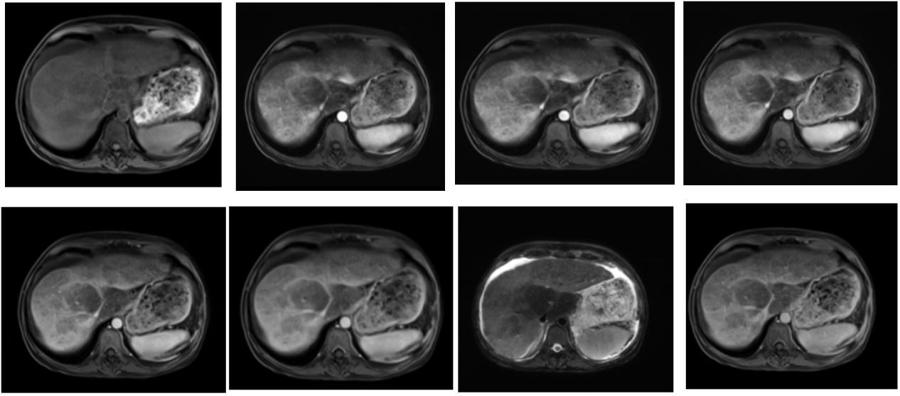

腹部-肝脏MRI,TWIST-VIBE以其超快的扫描速度,可以精确捕捉肝脏病变的血供信息,为诊断提供更准确的信息。